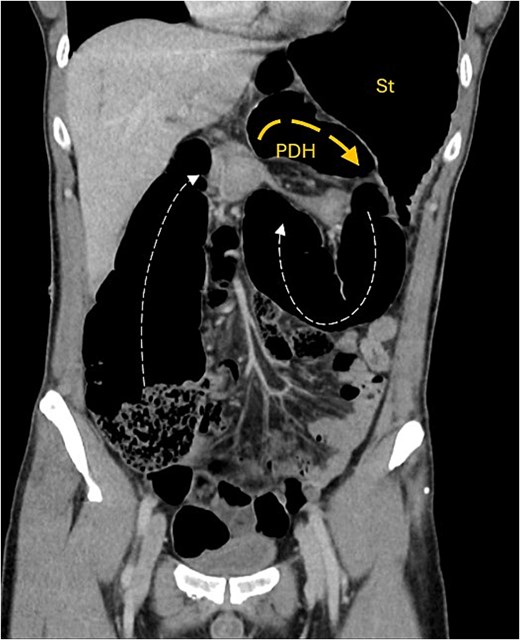

A contrast-enhanced computed tomography (CT) scan of the abdomen and pelvis demonstrated a large bowel obstruction with a transition point at the distal transverse colon with swirling of the mesentery. Downstream large bowel was collapsed. Upstream dilatation included the terminal ileum suggested an incompetent ileo-caecal valve. The gastric antrum was also involved in the internal hernia, resulting in gastric outlet obstruction. See Figs 1–5.

Coronal CT image showing obstructed transverse colon (Tx) path (small dash arrow), looping posteriorly through narrow hernia neck into anterior PDH containing Tx colon segment (wide dash arrow). Stomach (st) is distended.

Intestinal obstruction is a common presentation but paraduodenal hernia is an uncommon cause of obstruction. It more frequently results in small rather than large bowel obstruction [1–8].